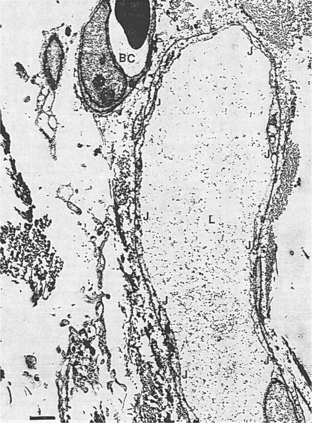

The vessel walls of these initial lymphatics are one cell thick, formed by overlapping endothelial cells with many loose junctions between cells opening and closing (Fig. 13-2). This action allows for movement of water and proteins into the vessel and prevents the escape of protein into the interstitium during the compression of the initial lymphatics.

Figure 13-2 An initial lymphatic (L) in a quiescent (at rest or inactive) tissue. Many closed (narrow or tight) junctions (J) are evident. A blood capillary (BC) is shown for comparison of size, endothelial opacity, and other characteristics. The bar at the lower left (1 μm) is provided to give the viewer size perspective. (From Casley-Smith JR, Casley-Smith JR: Modern treatment for lymphoedema, ed 5, Adelaide, Australia, 1997, Lymphoedema Association of Australia. Modified from Casely-Smith JR: Br J Exp Path 46:35-49, 1965.) Lymphoedema Association of Australia